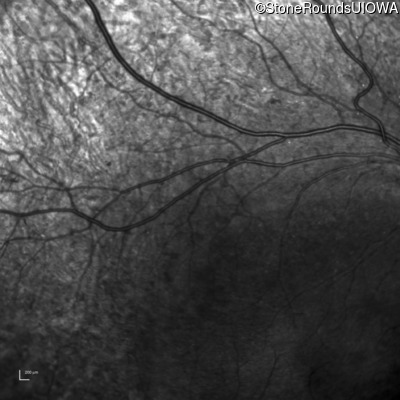

Infrared Fundus Photograph - Left - 20/20 -1

Exemplar